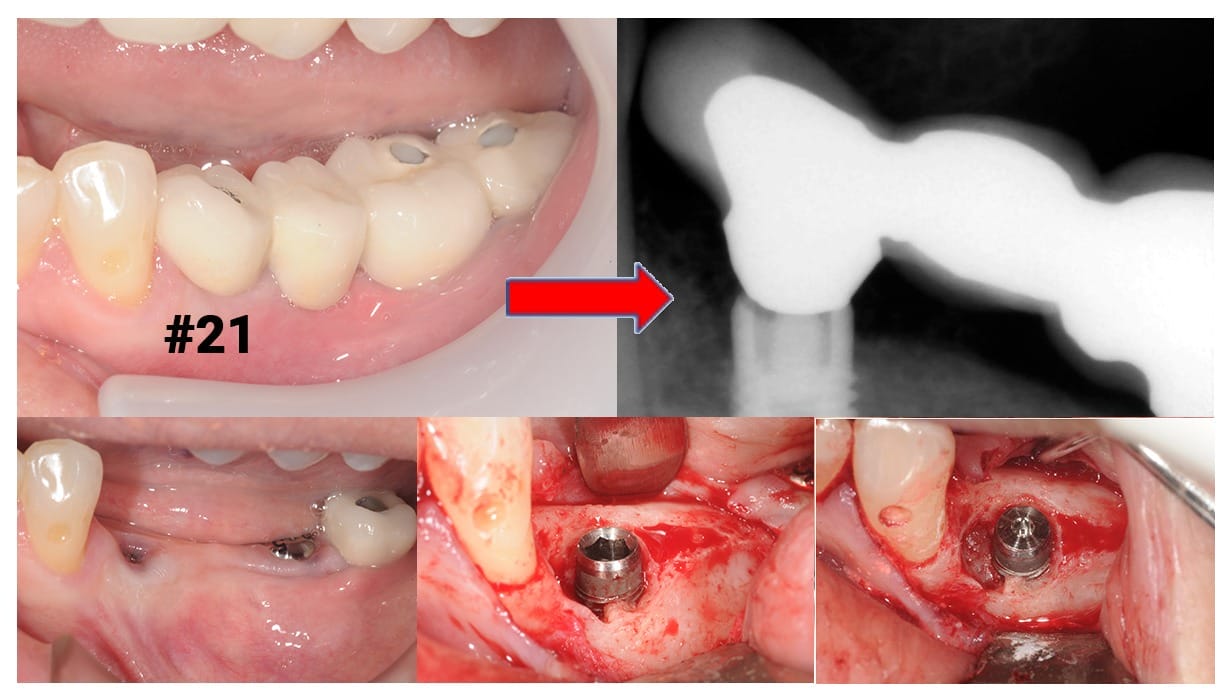

Combined with radiographs, other parts of the clinical exam should include testing for mobility in the implant crown as well as the fit of these components. Evaluating for soft and hard tissue deficiencies, or other signs of inflammation, and assessing for a healthy occlusion are all key parts of the dental implant exam (Figure 3). In addition to consistent dental hygiene care, maintenance recommendations should include a yearly evaluation visit with the surgeon who placed the implant for optimal health!

Figure 3: